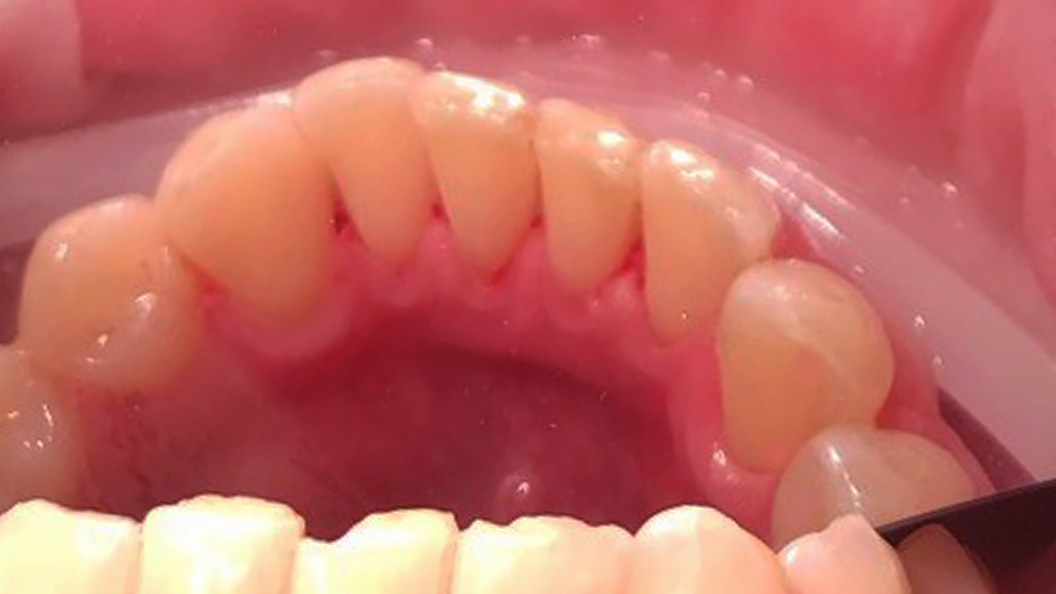

До и после лечения

Пациент обратился с жалобой на наличие зубных отложений и кровоточивость во время чистки зубов. Во время осмотра были выявлена над- и поддесневые отложения. Маргинальная десна отечна и гипермирована, при зондировании кровоточит.

Ход лечения:

- удаление над- и поддесневых отложений с помощью УЗ-аппарата

- профессиональная чистка зубов пастой Detarine Z